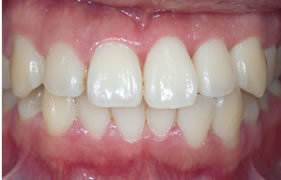

症例2

治療の特徴(患者Y様)

初診 2016年5月17日 / 経過 2018年7月2日

| 治療期間 | 2年2カ月 |

|---|---|

| 費用 | 保険内治療 |

| オペ費用 | 1ブロック約9,000円(3割負担) |

| 治療のデメリット | 歯内退縮が見られる。知覚過敏の症状が出ることがある。 |